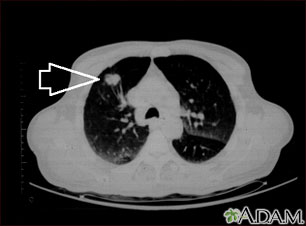

A chest CT (computed tomography) scan is an imaging method that uses x-rays to create cross-sectional pictures of the chest and upper abdomen.

A CT scan quickly creates detailed pictures of the body. The test may be used to get a better view of the structures inside the chest. A CT scan is one of the best ways of looking at soft tissues such as the heart and lungs.

- When a tumor or mass (clump of cells) is suspected, including a solitary pulmonary nodule seen on a chest x-ray

A chest CT may show many disorders of the heart, lungs, mediastinum, or chest area, including:

- Tumors, nodules, or cysts in the chest